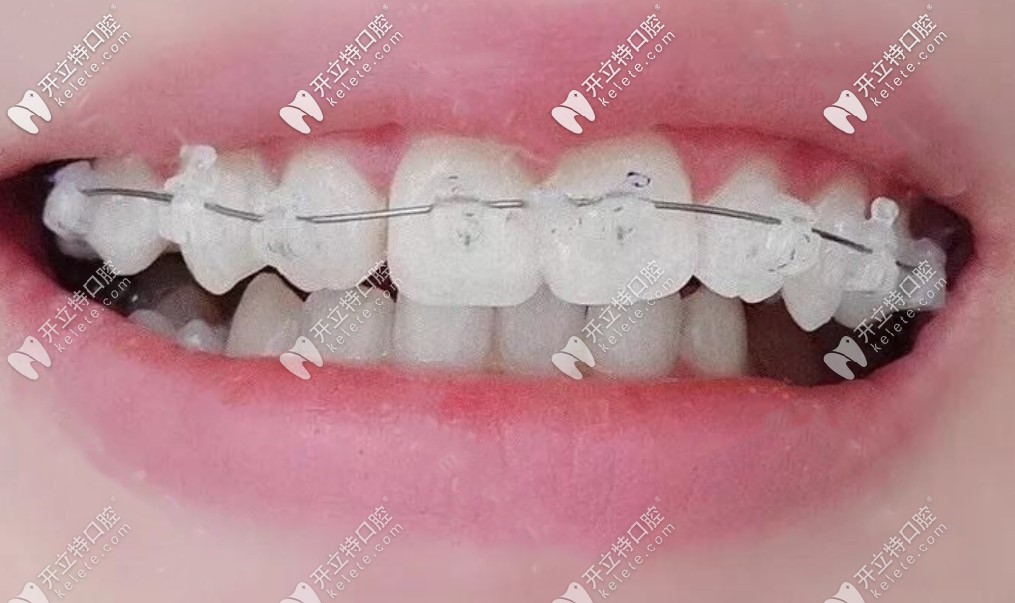

【矯正牙套】:陶瓷自鎖托槽矯正

我戴上陶瓷自鎖托槽效果圖▼

我戴上陶瓷自鎖托槽效果圖